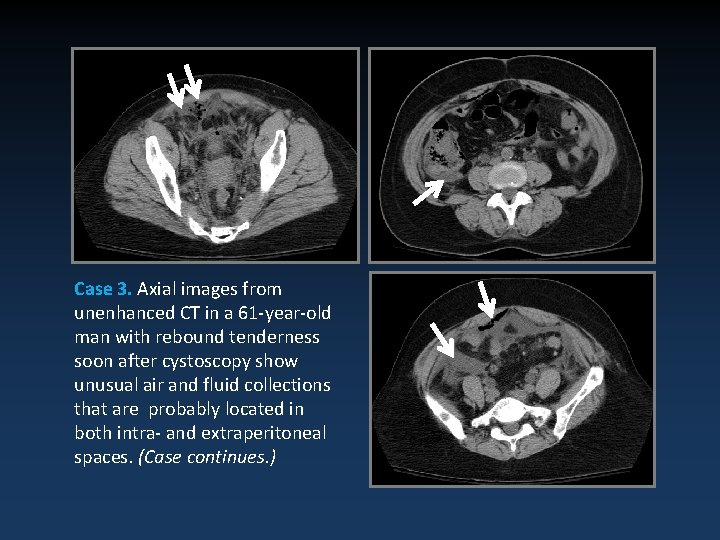

Case 3. Axial images from unenhanced CT in a 61 -year-old man with rebound tenderness soon after cystoscopy show unusual air and fluid collections that are probably located in both intra- and extraperitoneal spaces. (Case continues. )

Case 3 (continued). Repeat CT cystography shows extravasated contrast solution in both extraperitoneal and intraperitoneal spaces, findings indicative of a mixed bladder rupture. Note that the contrast material in the intraperitoneal space is less concentrated than that in the extraperitoneal space.